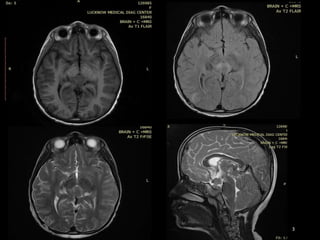

HISTORY

• 9 year old female patient present with

Headache and

Numbness & pain in both upper and lower limbs.

IMAGING FINDINGS

MR FINDINGS

• Iso- to slightly hyperintense to cortex on T1- and T2WI.

• T2* (GRE, SWI) may show “blooming” due to intratumoral

calcification.

• Enhancement is strong and usually homogeneous .

• Because of their high cellularity, germinomas may show

restricted diffusion.

CASE SUMMARY

• 9yr old female patient present with headache and

numbness of limbs

• On imaging shows Relatively well define

hetrogenous enhancing mass lesion in pineal region

and concurrent suprasellar mass with

leptomeningeal spread

• Likely Diagnosis is GERMINOMA

• HPE is awaited